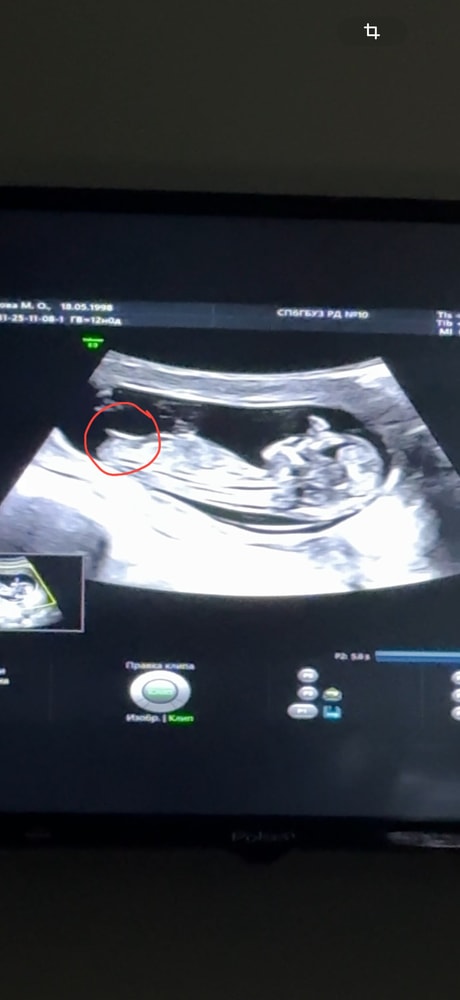

Первый скрининг был хороший, носовая кость визуализировалась, Нипт все риски низкие, второй скрининг носовая кость 5,6мм (норма для 21 недели 5,8-7,4), гипоплазия плаценты 18,1 (норма 21 недели 22,59-28,17) уснуть не могу после этого скрининга, завтра к врачу иду 😔